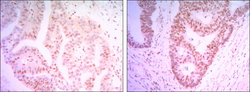

Immunohistochemistry

LS-C169234 IHC